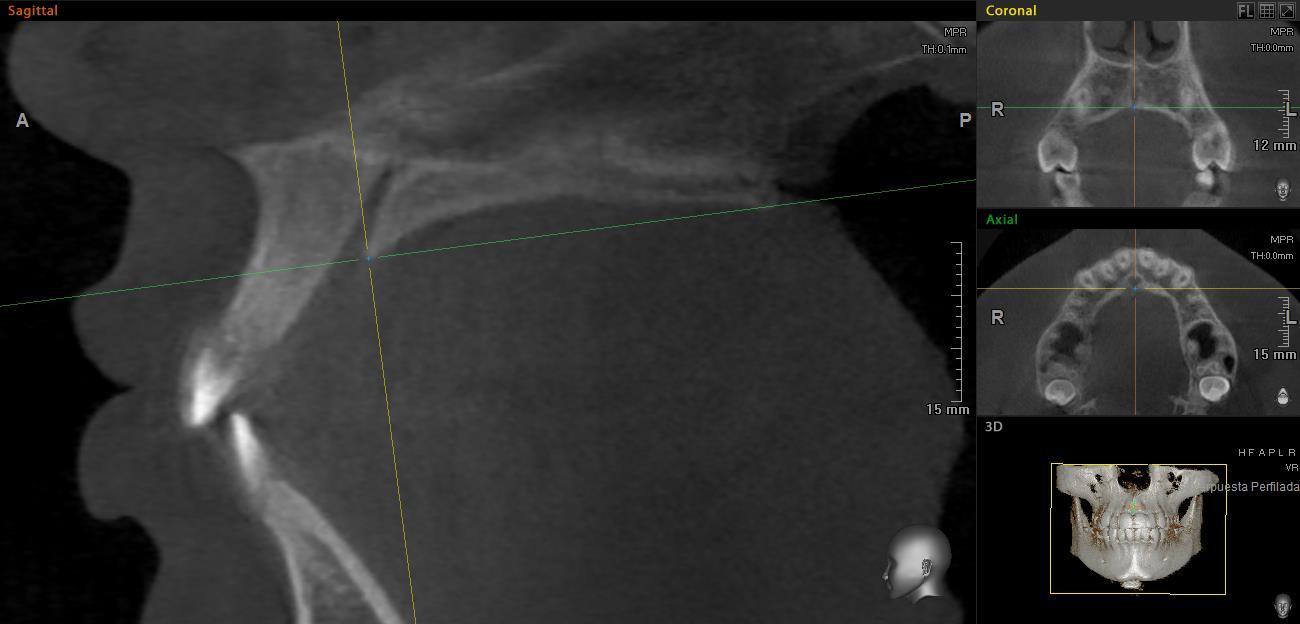

Las imágenes fueron orientadas utilizando el mismo protocolo. En el corte sagital, la intersección entre el plano sagital y coronal se coloca sobre el borde posterior del foramen incisivo, de manera que el plano axial coincida con la espina nasal posterior (Figura 1).

En el corte sagital, las mediciones se realizaron de los 0 a los 24mm, con intervalos de 3 mm entre cada una, con la primera medición en el borde posterior del foramen incisivo (Figura 2). Las mediciones del grosor palatino se realizaron en el corte coronal a los 2, 4, 6 y 8mm, de la sutura media palatina hacia ambos lados (Figura 3).